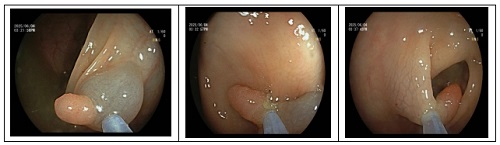

内镜下开展的手术

1. 内镜下息肉摘除术